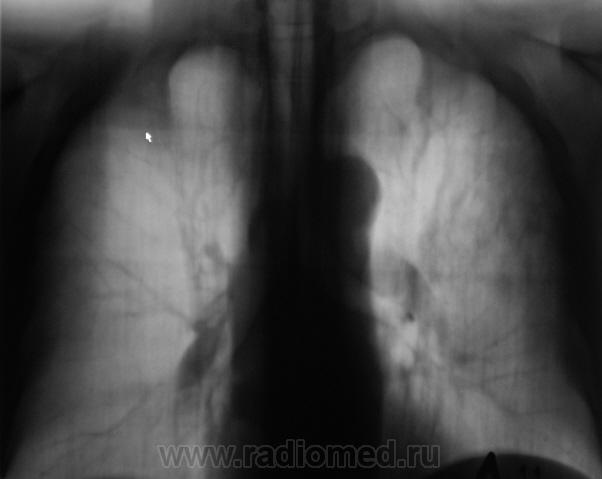

При расшифровке флюорограмм пациент "взят на контроль". Жалоб пациент не предъявляет. Подняли "архив", флюорограмма за 2009 г. - "норма".

Произвели стандартное дообследование.

Томограммы.